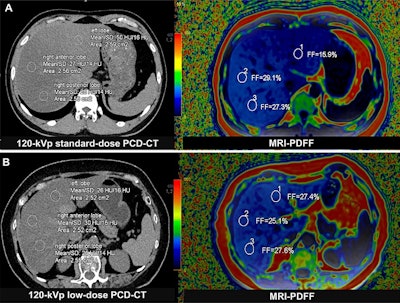

Liver fat content measurement with photon-counting CT and MRI-based proton density fat fraction (PDFF). Three regions of interest (circles) were delineated in the peripheral areas of the left, right anterior, and right posterior lobes of the liver. (A) Representative axial unenhanced 120-kVp standard-dose CT image (left) and corresponding MRI scan (right) in a 33-year-old man (body mass index, 26.2) diagnosed with metabolic dysfunction-associated steatotic liver disease (MASLD) in the asymptomatic cohort. (B) Representative axial unenhanced 120-kVp low-dose CT image (left) and corresponding MRI scan (right) in a 69-year-old woman (body mass index, 24.6) in the MASLD cohort. Body mass index was calculated as weight in kilograms divided by height in meters squared.Image courtesy of the RSNA.

According to the findings, across all comparisons in asymptomatic patients, photon-counting CT fat fractions (CTFF) demonstrated excellent agreement with MRI proton density fat fractions (PDFF) (mean bias values < 1%). In addition, CTFF error was not influenced by tube voltage, radiation dose, or body mass index. Agreement between CTFF and PDFF was also found in the MASLD cohort (mean bias, −0.2%).